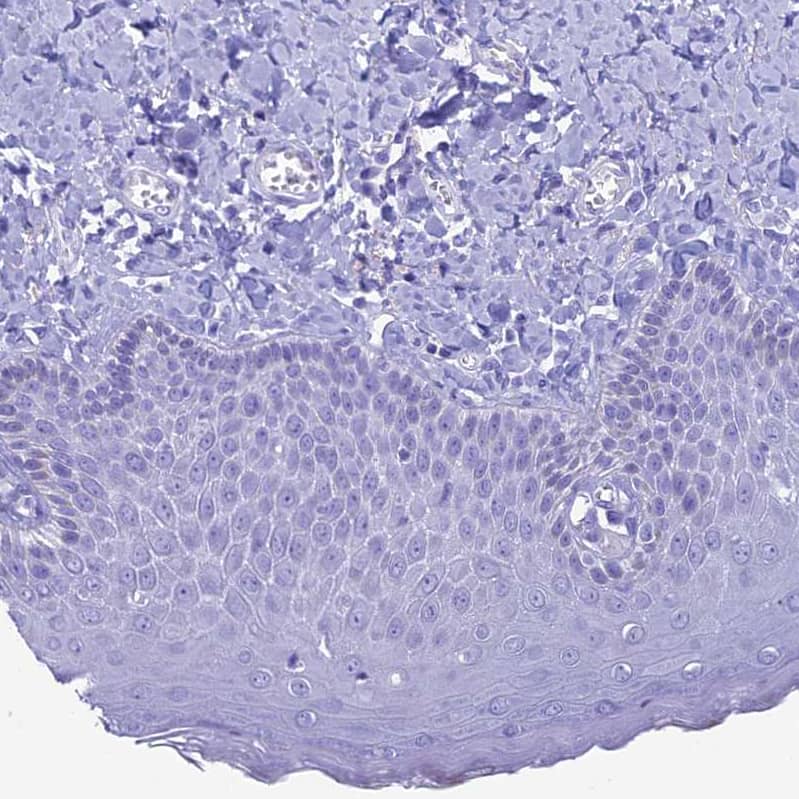

Immunohistochemistry-Paraffin: FAM169A Antibody [NBP1-93616] - Staining of human skin shows no positivity in squmaous epithelial cells as expected.

Staining of human skin shows no positivity in squamous epithelial cells as expected.